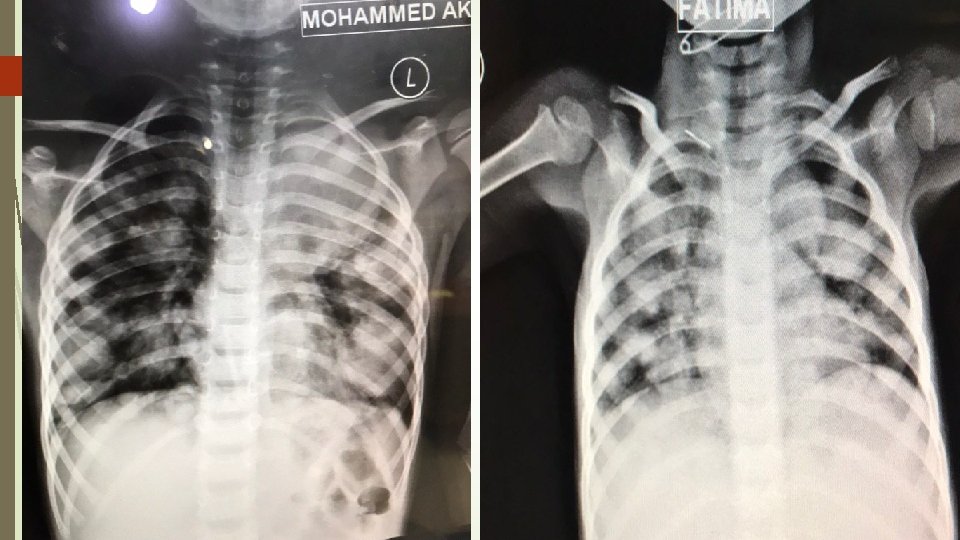

Pediatric imaging Learning objectives 1 Systemic approach interpretation